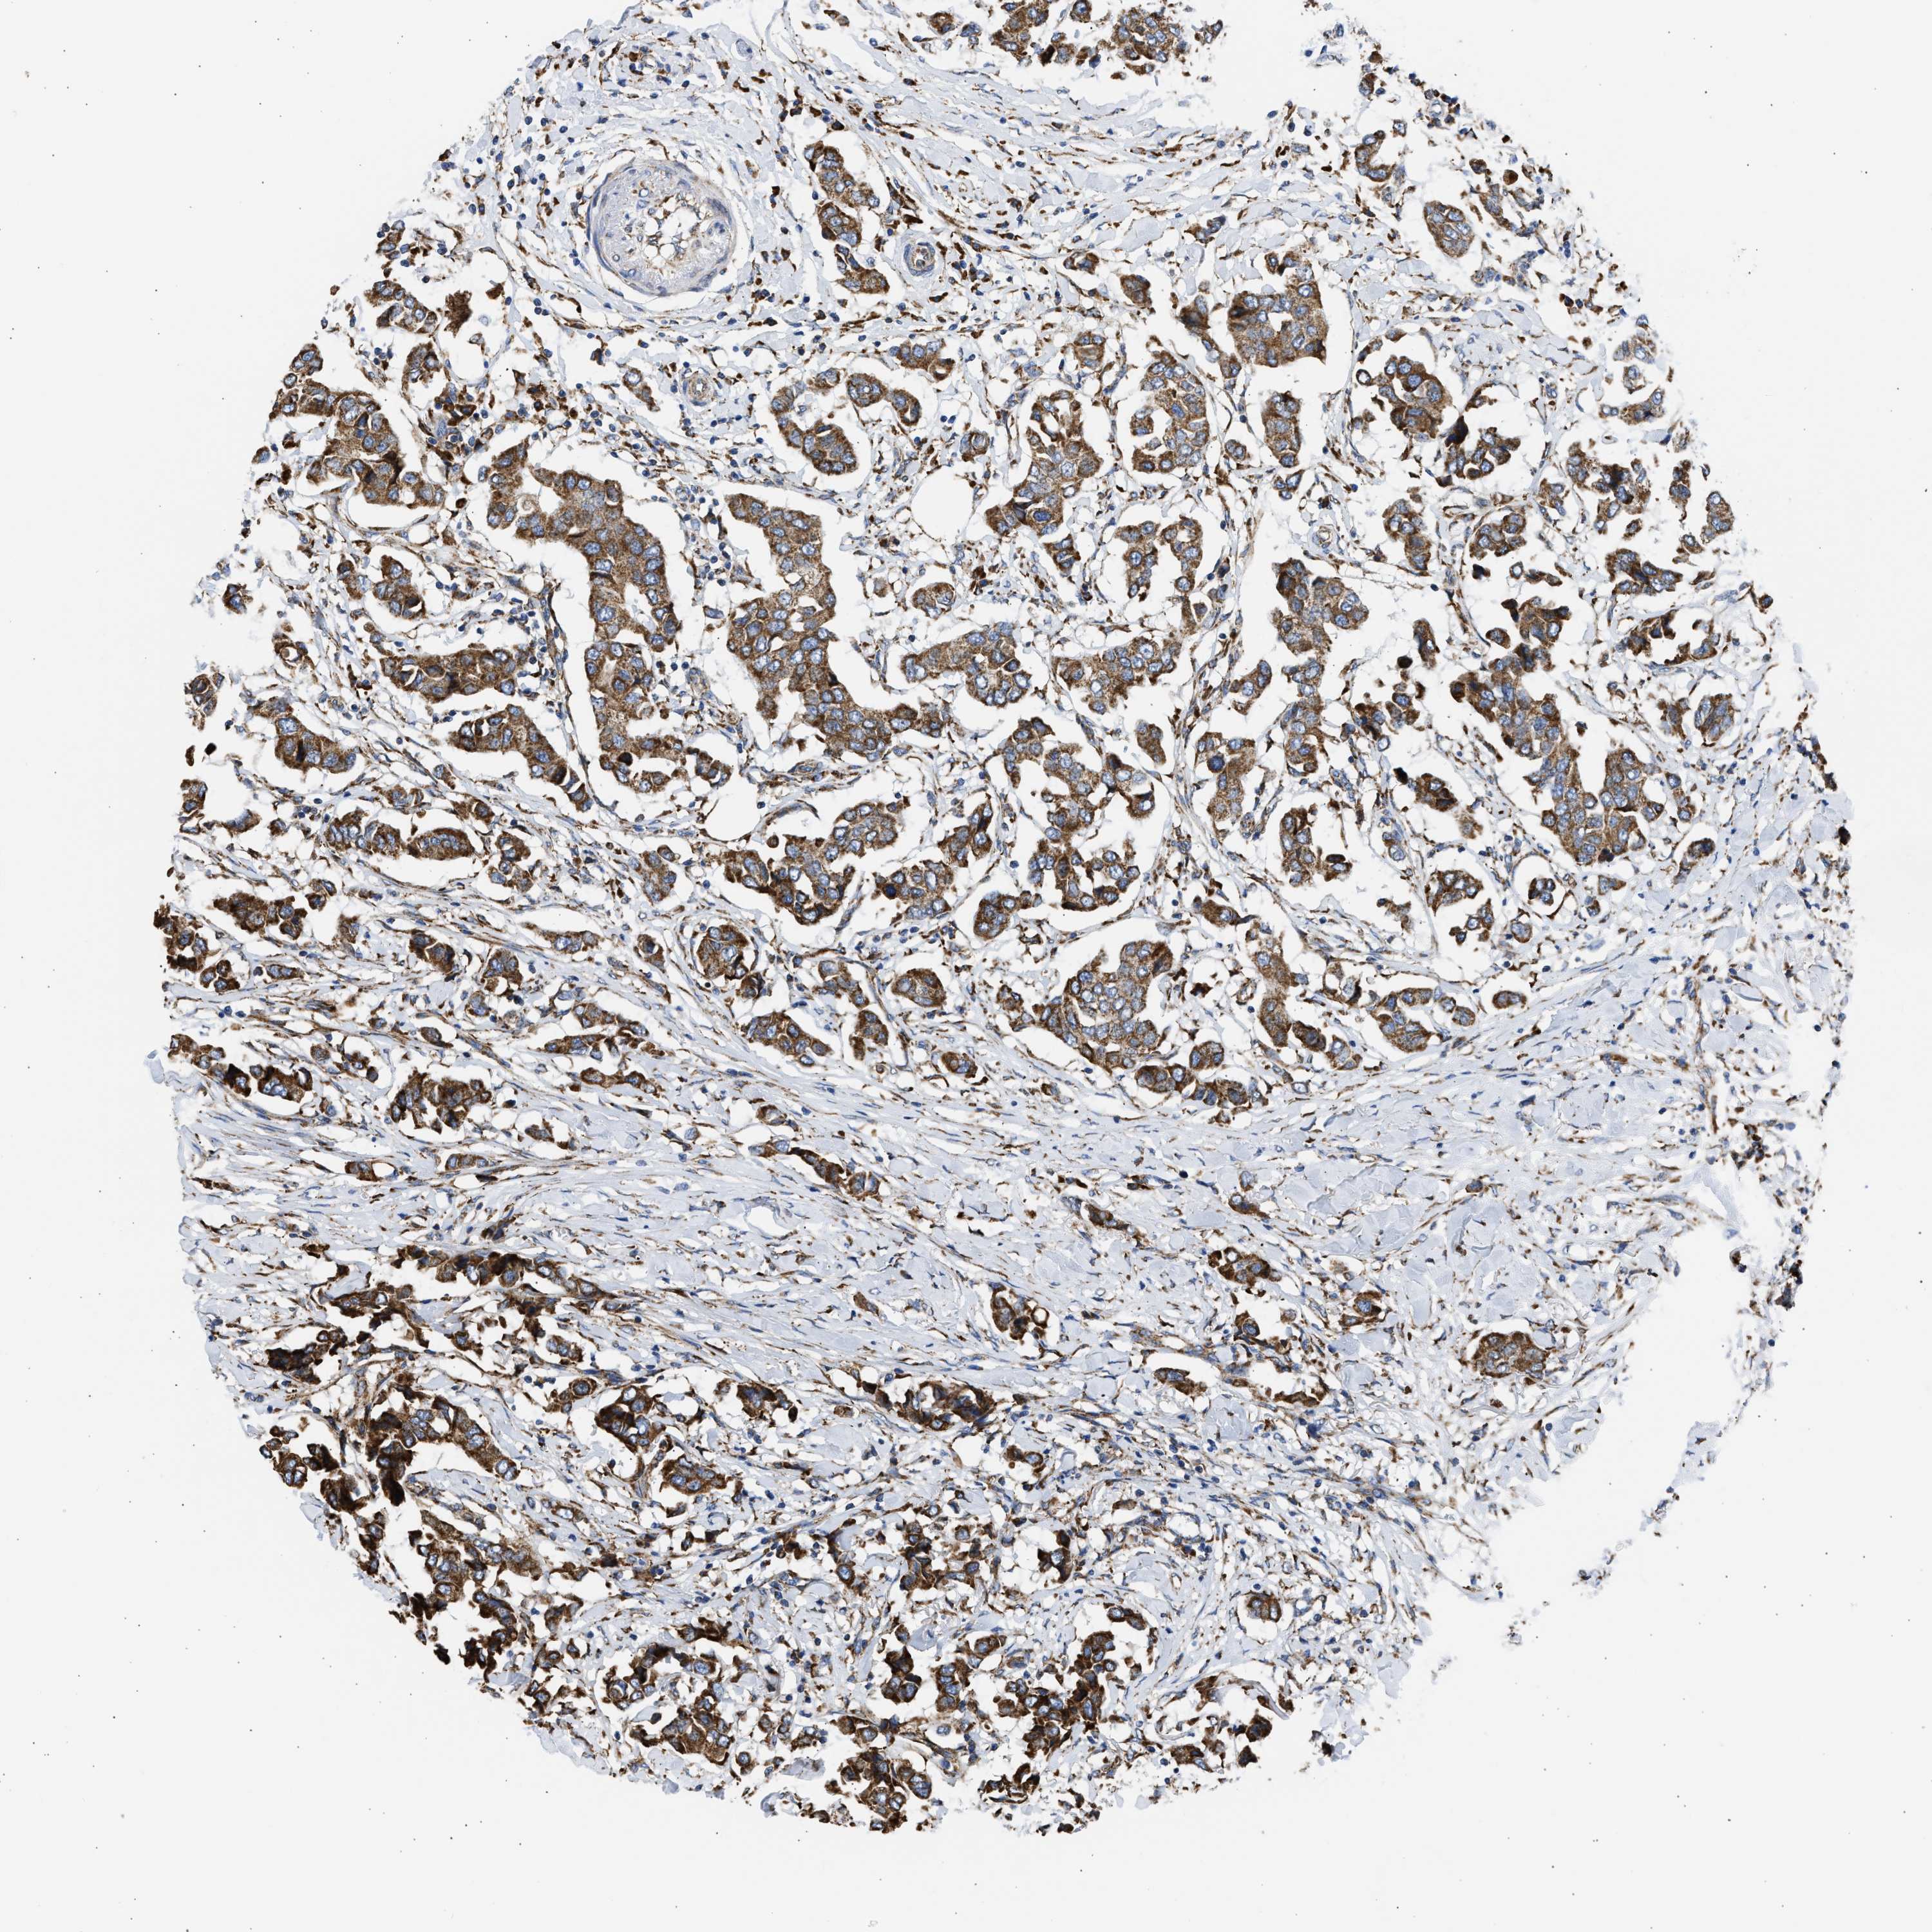

CANCER BREAST CANCER Show tissue menu

BRCA TCGA BRCA VALIDATION PROTEIN EXPRESSION